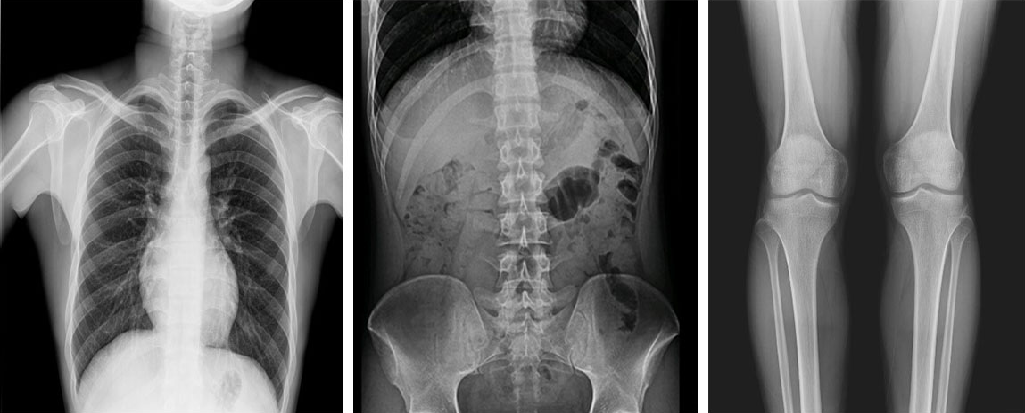

在功能上,動態(tài)DR已不再局限于簡單的拍片功能,而是集數(shù)字化攝影、數(shù)字化透視、數(shù)字化造影、數(shù)字化實時點片于一體,臨床用途廣泛,可應用于臨床各科室,如體檢科、內(nèi)科、外科、骨科、創(chuàng)傷科、急診科等。

與此同時,動態(tài)DR的成像視野與精度也勝于靜態(tài)DR。動態(tài) DR17×17 英寸方形幅面進行動態(tài)成像,能夠?qū)鹘y(tǒng)動態(tài)造影幅面小的問題全部解決,同時由于幅面較大,臨床操作技師能夠在一個大的幅面下觀察診斷,當看到病變部位時實時高清點片,從而很好地捕捉到病變點,也大大降低了檢查時間。

PLD8000系列數(shù)字透視攝影系統(tǒng)集數(shù)字化攝影、數(shù)字化透視、數(shù)字化造影、可視化點片等多種功能于一體,搭載高品質(zhì)高壓發(fā)生器、球管與平板探測器,確保性能穩(wěn)定的同時成就高清成像,同時提高機架自動化程度,并且配備智能化電動床體,帶來智能化、人性化操作體驗,全面滿足各級醫(yī)療機構(gòu)放射檢查需求。